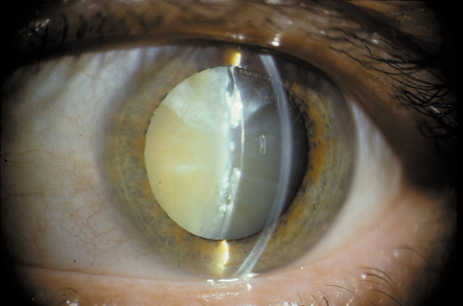

One can examine this type of cataract with direct illumination, using the narrow and broad beams of the slit-lamp to show the characteristic granular inner surface immediately in front of the posterior capsule (Fig. 13). The problem with this technique, however, is that patients may not tolerate any prolonged direct illumination because of the glare. Retroillumination is therefore more useful for revealing the outline of the opacity, since it is usually seen as an “island” in the center of the posterior capsule, which is further highlighted by the shadow cast by the opacities.33 However, in the early stages of this type of cataract, the dust-like particles that might be noticeable in the central posterior subcapsular area with direct illumination disappear or are difficult to see with retroillumination (Fig. 14). Eventually this “dusting” becomes dense enough to cast a shadow and thus appear on retroillumination. The smooth orange background of the fundus helps to highlight the rough, irregular pseudopodia-like edges of the central opacity. In advanced stages, the PSC may become a thick, calcified plaque (Fig. 15). During surgery, excessively vigorous scraping or vacuuming of the calcified opacity can lead to rupture of the posterior capsule. Usually, small remnants that are left behind after surgery are reabsorbed and do not interfere with vision; otherwise, they are easily treated with a neodymium : yttrium (Nd:YAG) aluminum garnet laser. Pathologic evidence suggests that most PSCs result from the migration of bow region cells into the potential space (along with accumulated cellular debris) between the posterior capsule and the cortex.34–36

Fig. 13. Direct slit-lamp illumination of a PSC, showing an irregular granular surface in front of the posterior capsule.